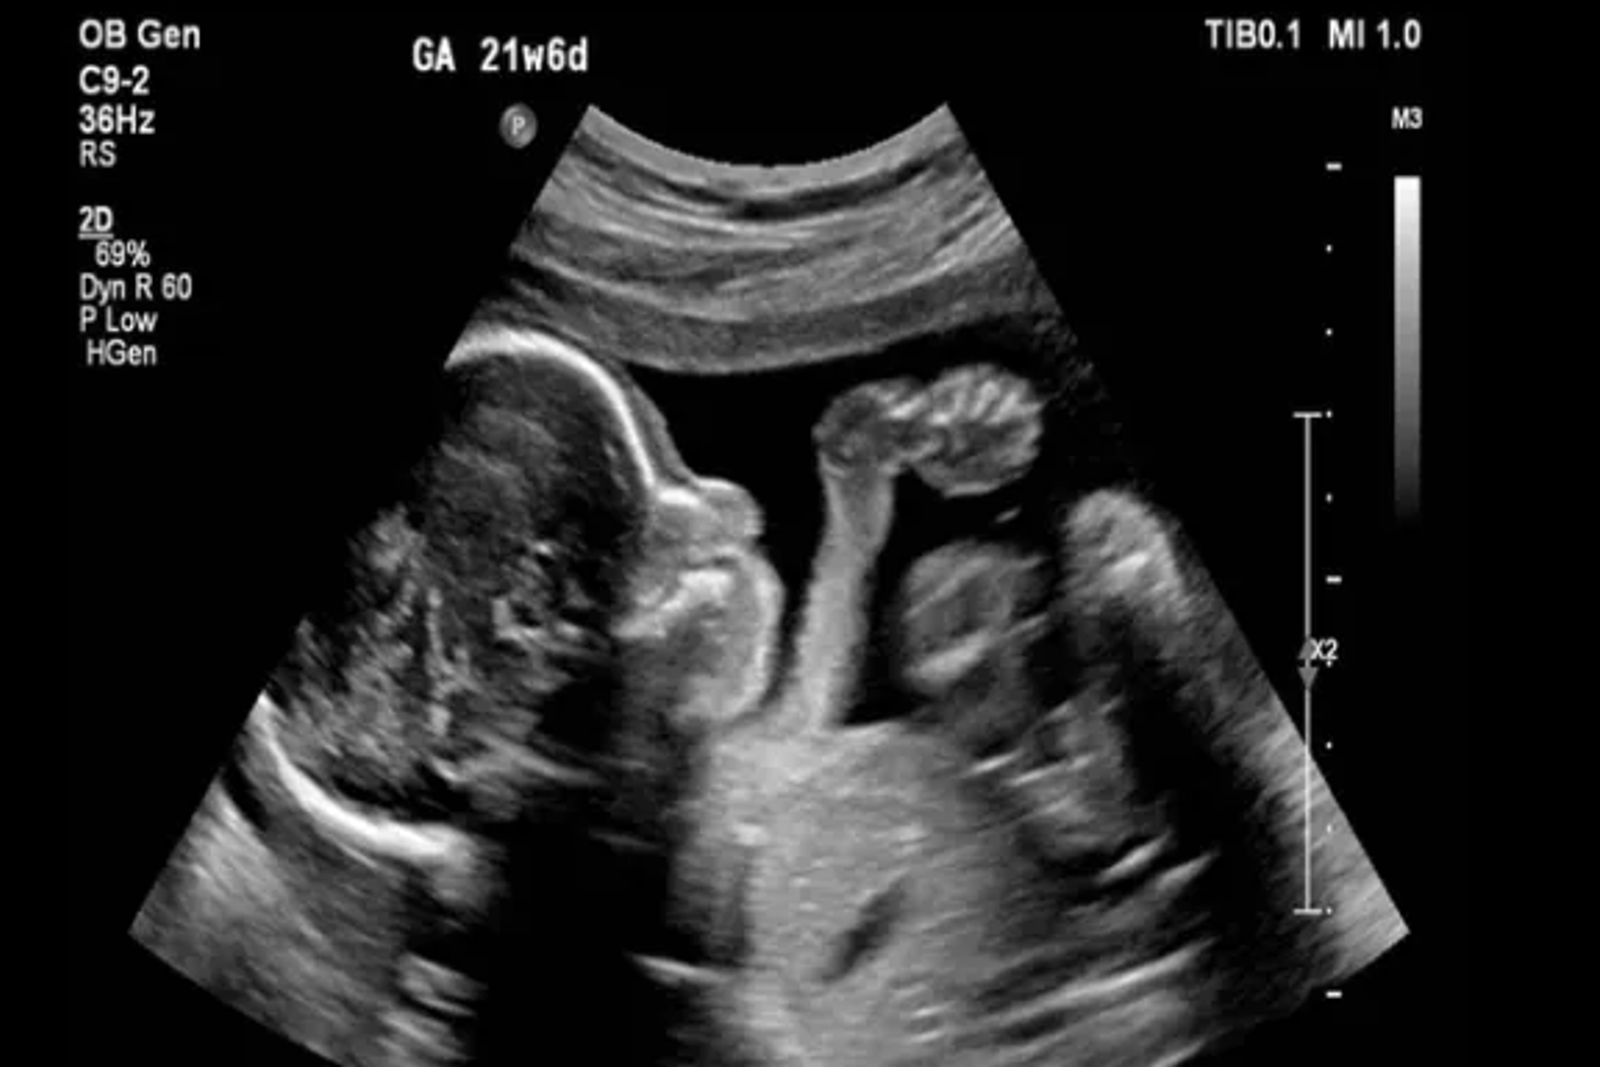

پژوهشگران ایتالیایی و فنلاندی در پژوهشی تازه دریافتند مصرف داروی ضد افسردگی فلوکستین، معروف به پروزاک، در دوران بارداری و شیردهی میتواند رشد طبیعی مغز نوزادان را مختل کند و آنها را در معرض خطر ابتلا به افسردگی و اختلالات حافظه قرار دهد.

به گزارش دیلی میل، این یافتهها که در نشریه «مولکولار سایکایتری» منتشر شد، حاکی از آن است که هر گونه اختلال در روند زمانبندی شده و حساس رشد مغز جنین میتواند آسیبهای ماندگاری به ساختار مغز وارد کند؛ هرچند علائم آن ممکن است در بزرگسالی ظاهر شود.